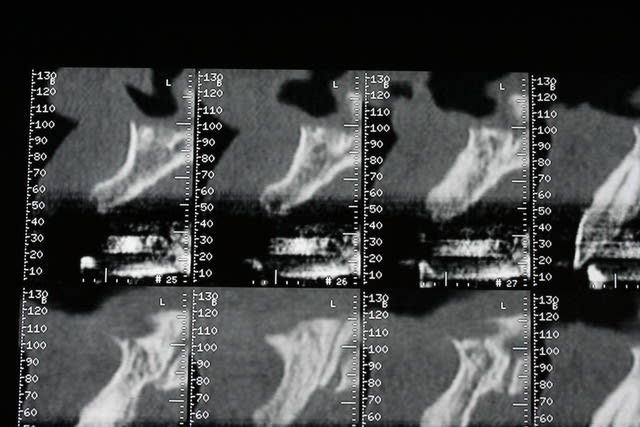

18/06/2009 à 21h12

bon, première salve...

photos du scanner...et avec la planche radio pour bien estimer le volume disponible

d'entrée de jeu, on peut se dire que çà va être plus coton pour la 22 que pour la 12 car on à moins d'épaisseur et la corticale est plus dense...